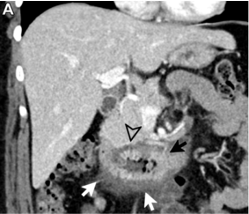

- Expansion of the space between the pancreatic head and duodenum is to be expected, with medial displacement of the pancreatic head and a laterally shifted duodenum- likely arising from the groove

- If both pancreas and duodenum are displaced in the same direction, the lesion is most likely located outside the groove

- Presence or absence of biliary and pancreatic duct obstruction degree and morphology of upstream ductal dilatation Effect on adjacent vascular structures -mesenteric and portal veins and the pancreaticoduodenal artery Rarer ancillary features such as abnormal air, hemorrhage, and fistulization can also be helpful if present.